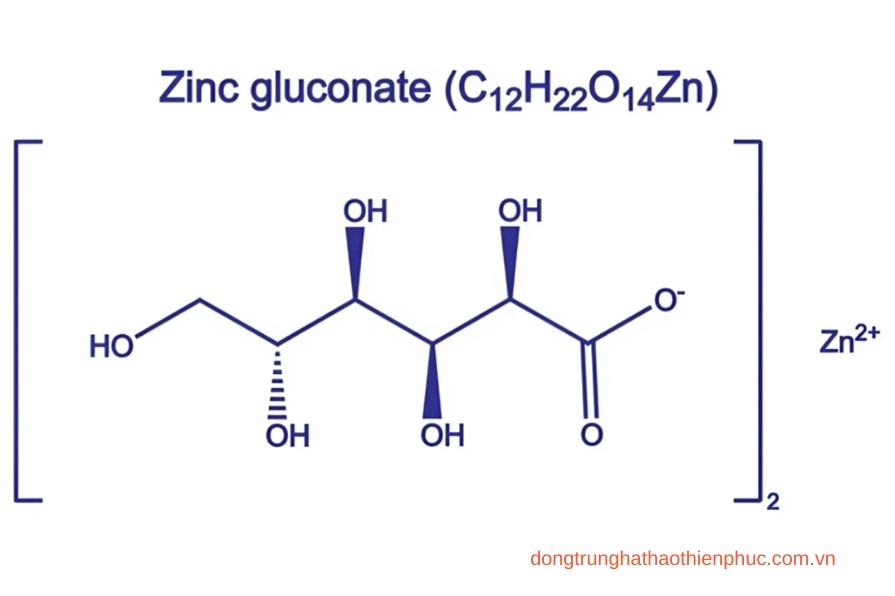

Kẽm Gluconate là một hợp chất chứa kẽm có vai trò quan trọng trong việc duy trì sức khỏe và cải thiện nhiều chức năng cơ thể. Trong sản phẩm viên bổ thận Banikha Thiên Phúc, Kẽm Gluconate được kết hợp với các thảo dược quý hiếm để tạo nên công thức tối ưu hỗ trợ bổ thận, tăng cường sinh lực và nâng cao sức đề kháng.